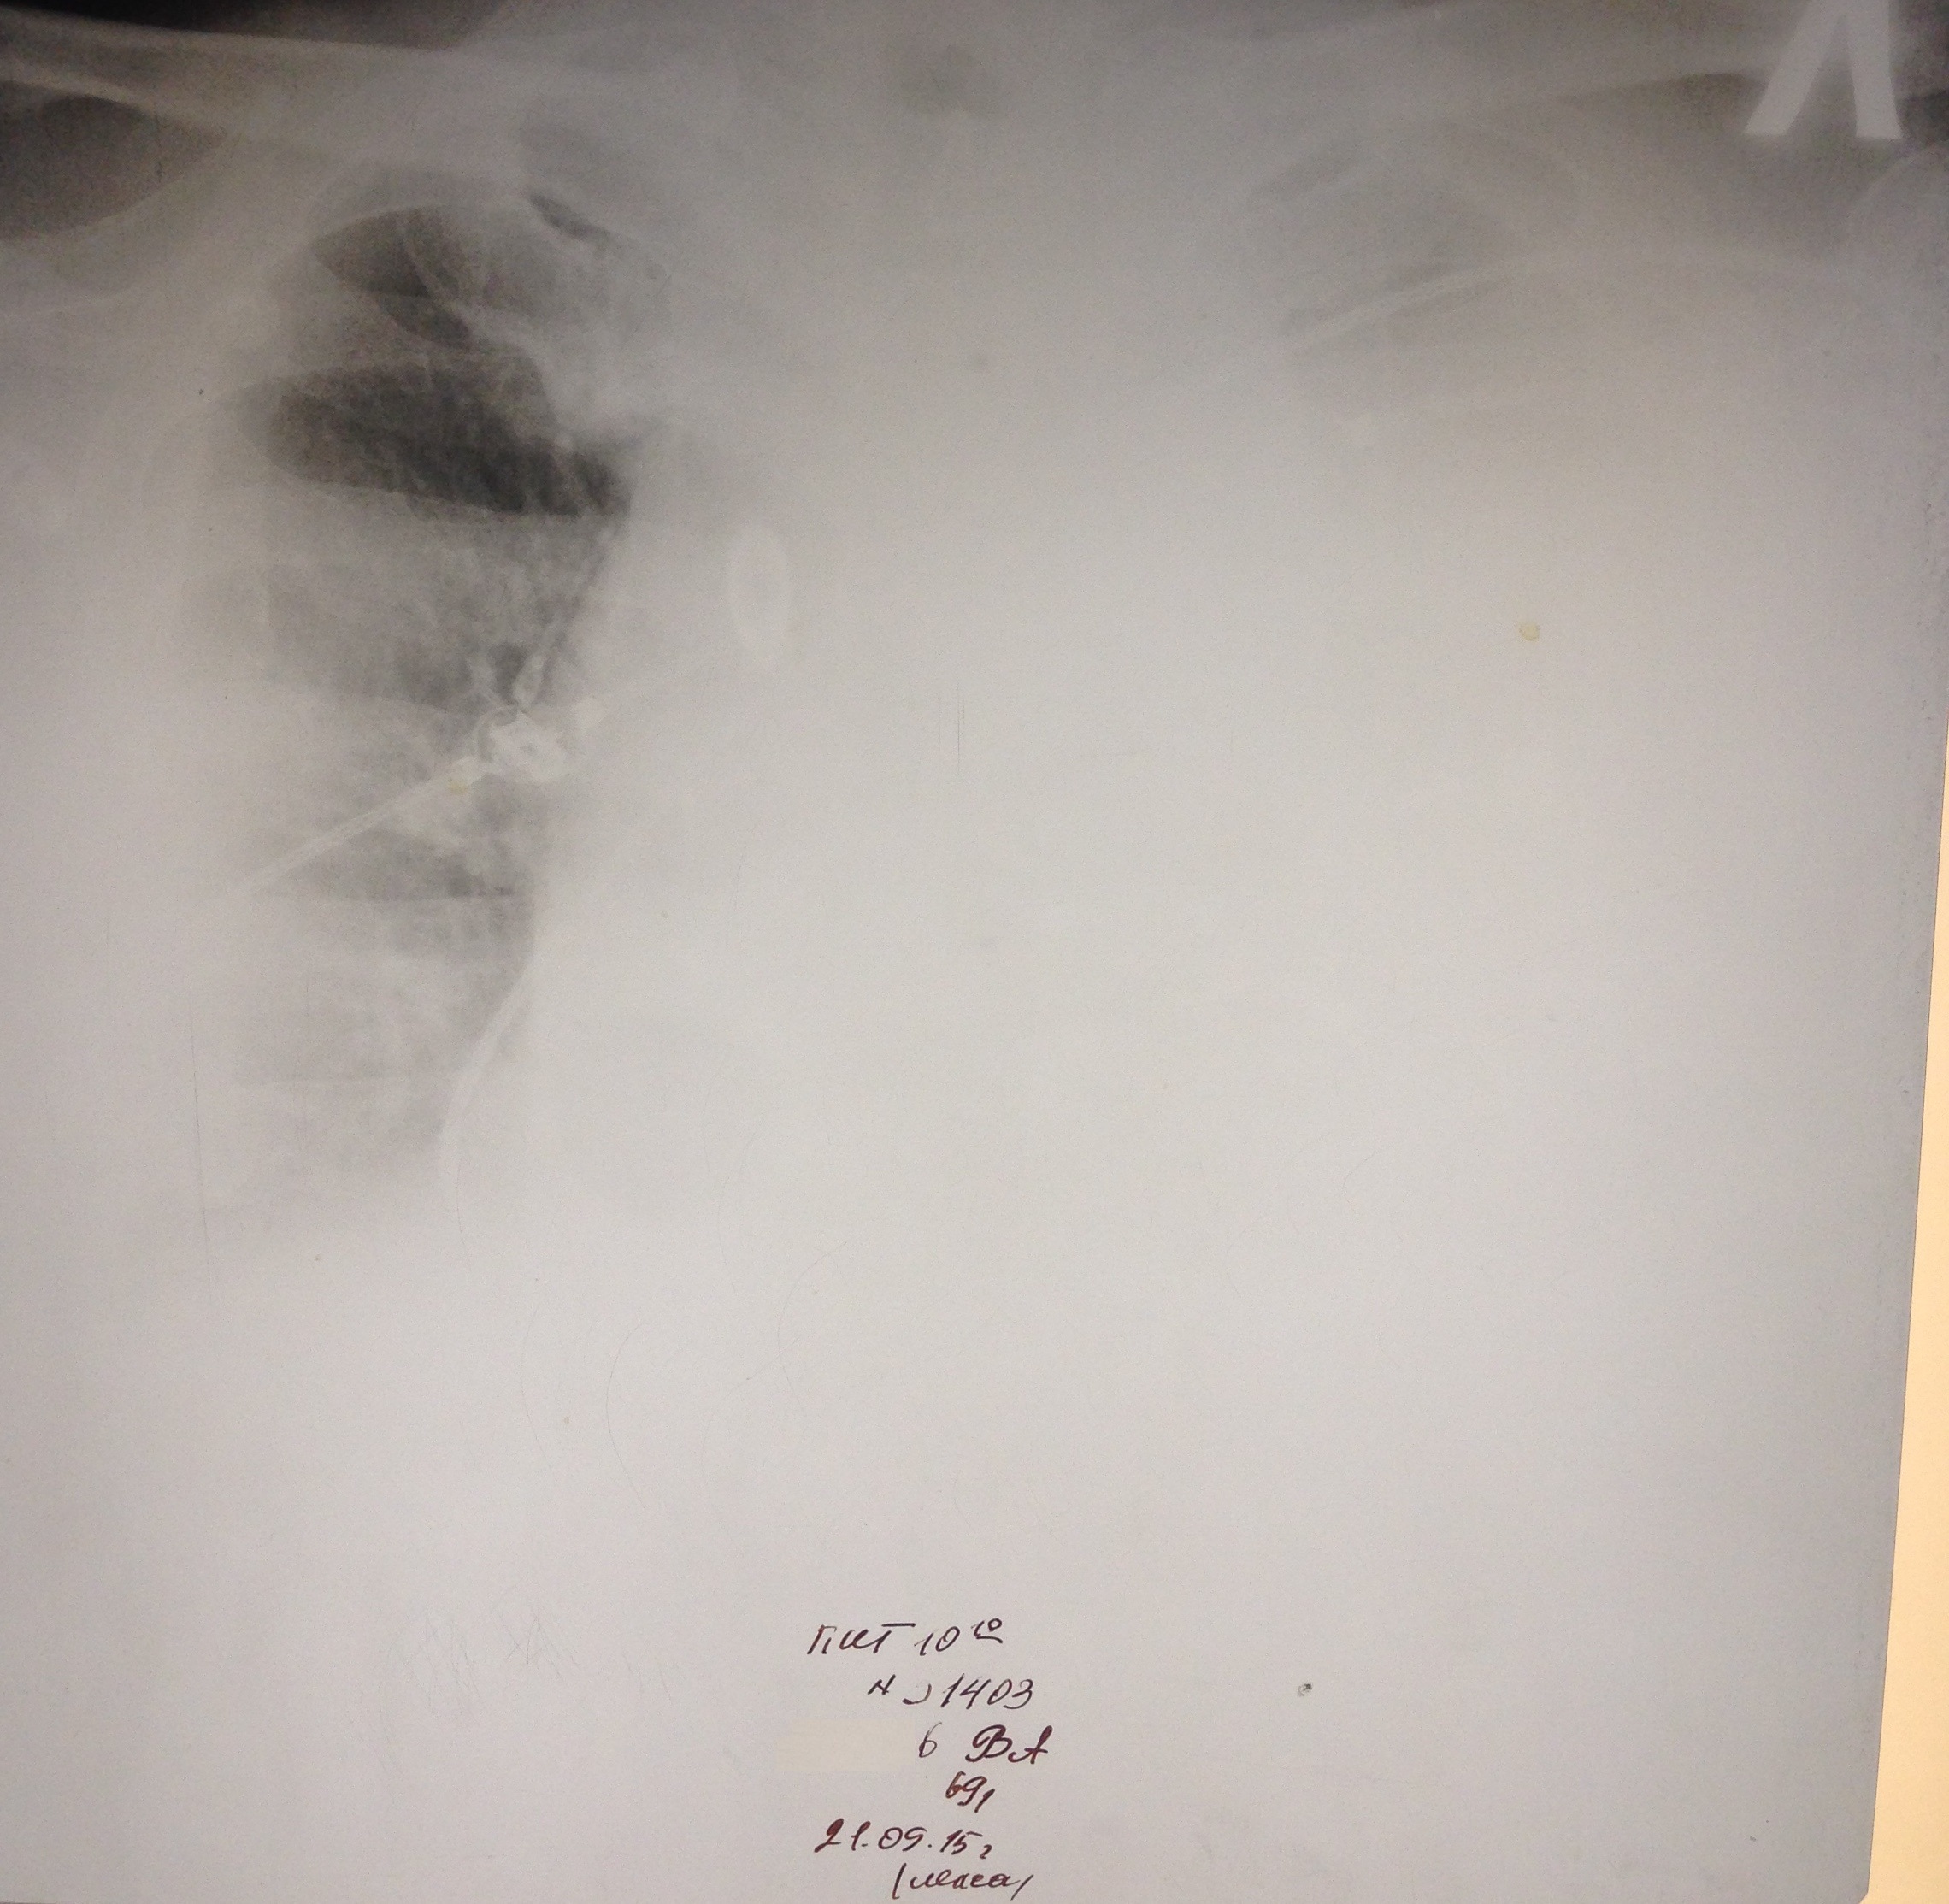

М, 69 лет. РАА. На первом снимке расширение срединной тени. На втором гемоторакс в результате прорыва крови из аорты в плевральную полость.

Ж 84 года. В маразме. РАА дуги и нисходящего отдела, доказана МСКТ. Поступила с болями в левом боку. На первом снимке левосторонний гемоторакс. На втором накопление жидкости до тотального уровня. На третьем после дренажа. Не оперирована. Выписана домой на 23 день госпитализации.